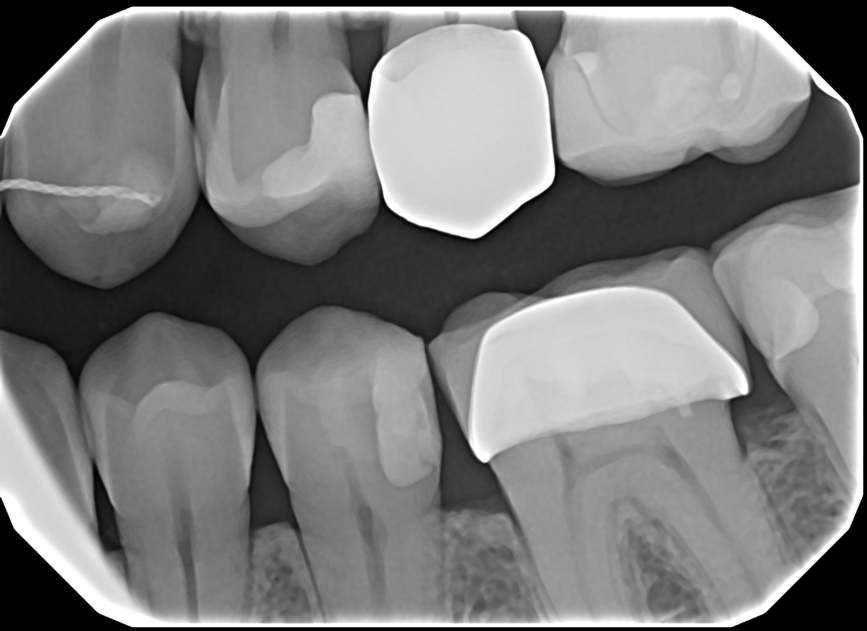

See The Clarity For Yourself

• Left Bitewing

• Mandibular Anterior

• Right Bitewing

• Maxillary Anterior

Produces a crystal clear image for confident diagnoses

Crisp Images, Low Exposure

The low-noise design delivers exceptional clarity even at lower doses. Keeps patients safer while improving diagnostic confidence.